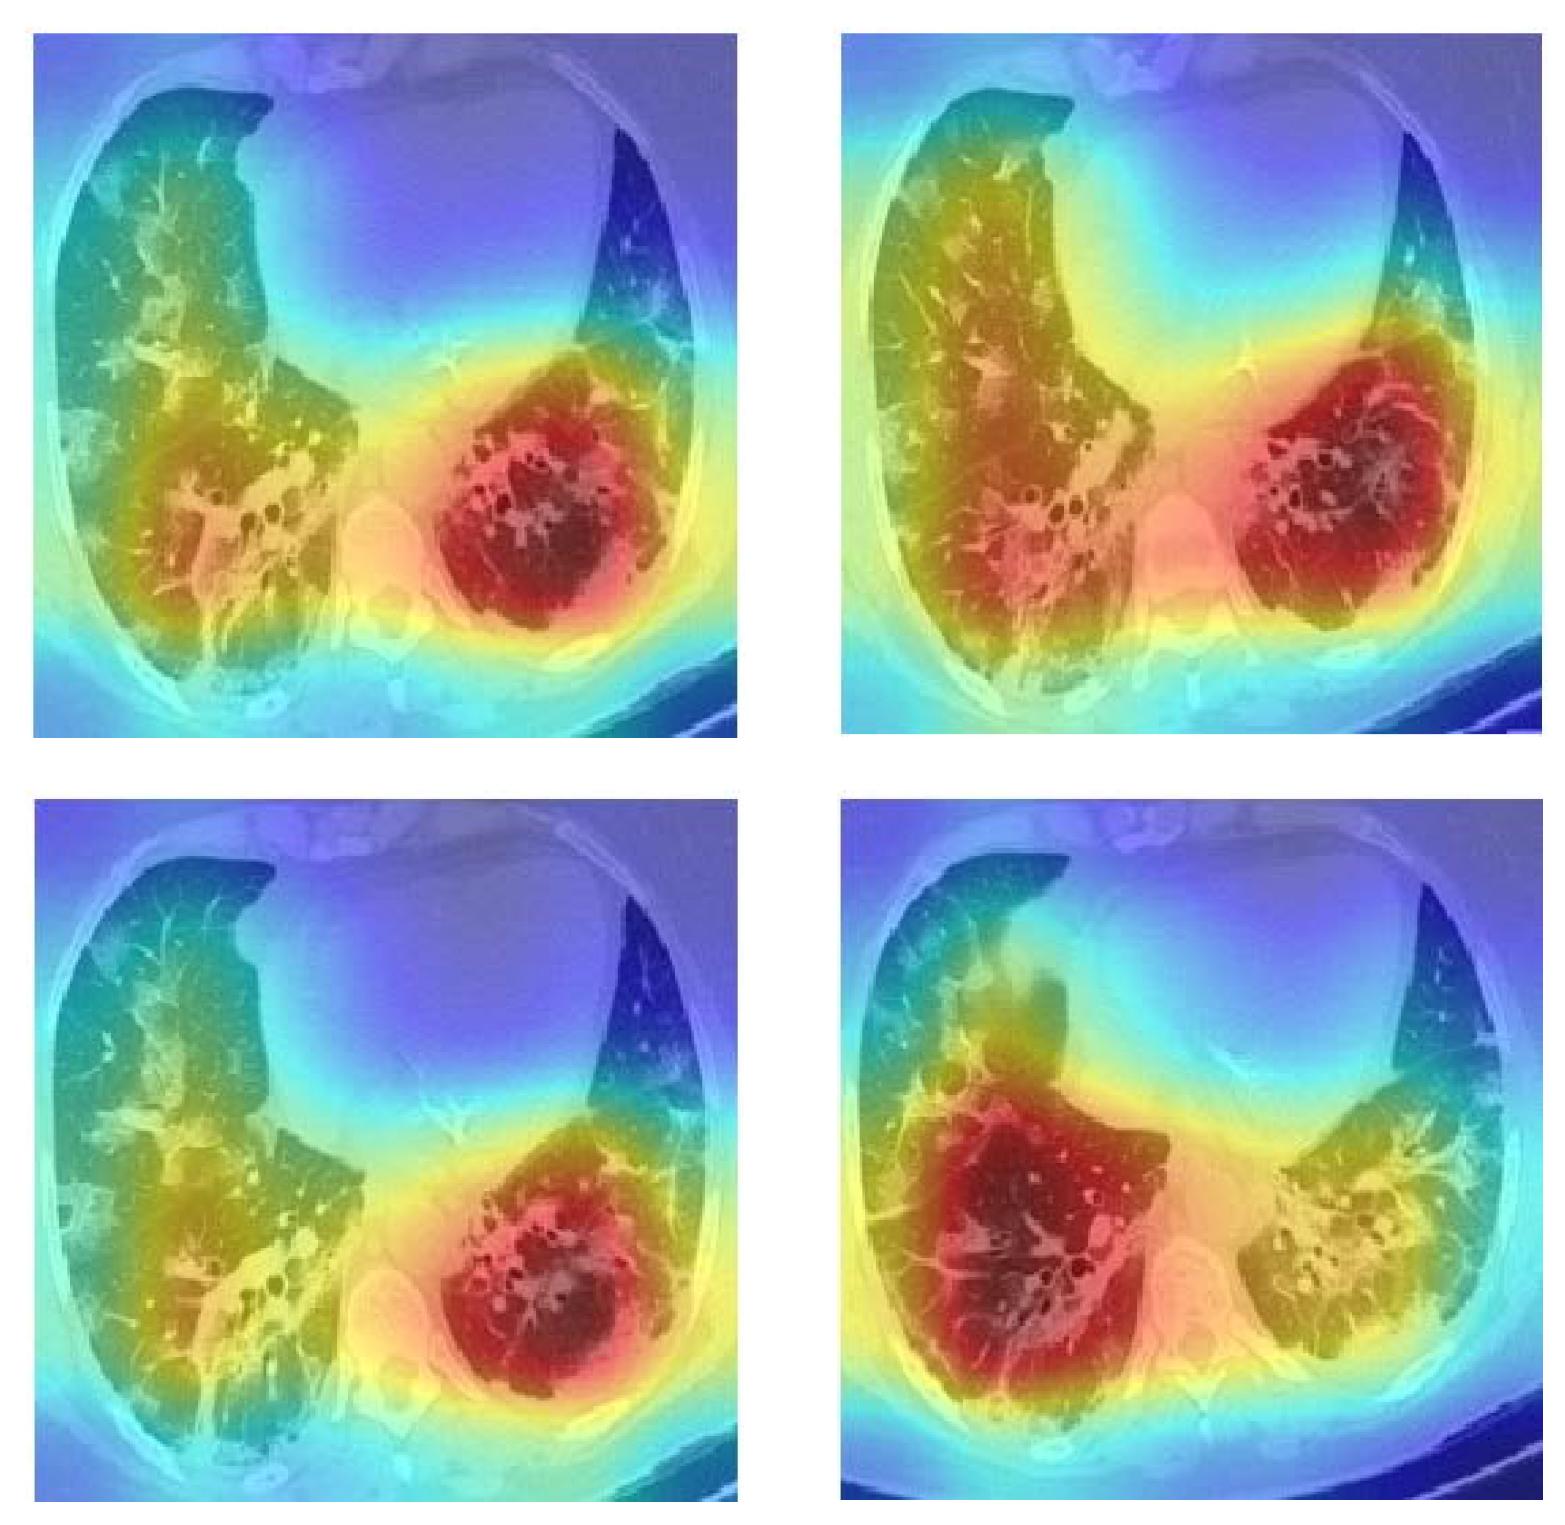

4.6. Explainability of the CGENet

We wanted to find out why the CGENet could produce accurate predictions, so the Grad-CAM was employed to visualize the model’s attention [33]. We provide several heat maps of the COVID-19 examples in Figure 6. The CGENet paid more attention to the red and yellow regions and disregarded the blue regions when making predictions. We can see that the CGENet can roughly locate the potential lesion areas to make accurate predictions.

Figure 6. Grad-CAM heat maps of COVID-19 cases.